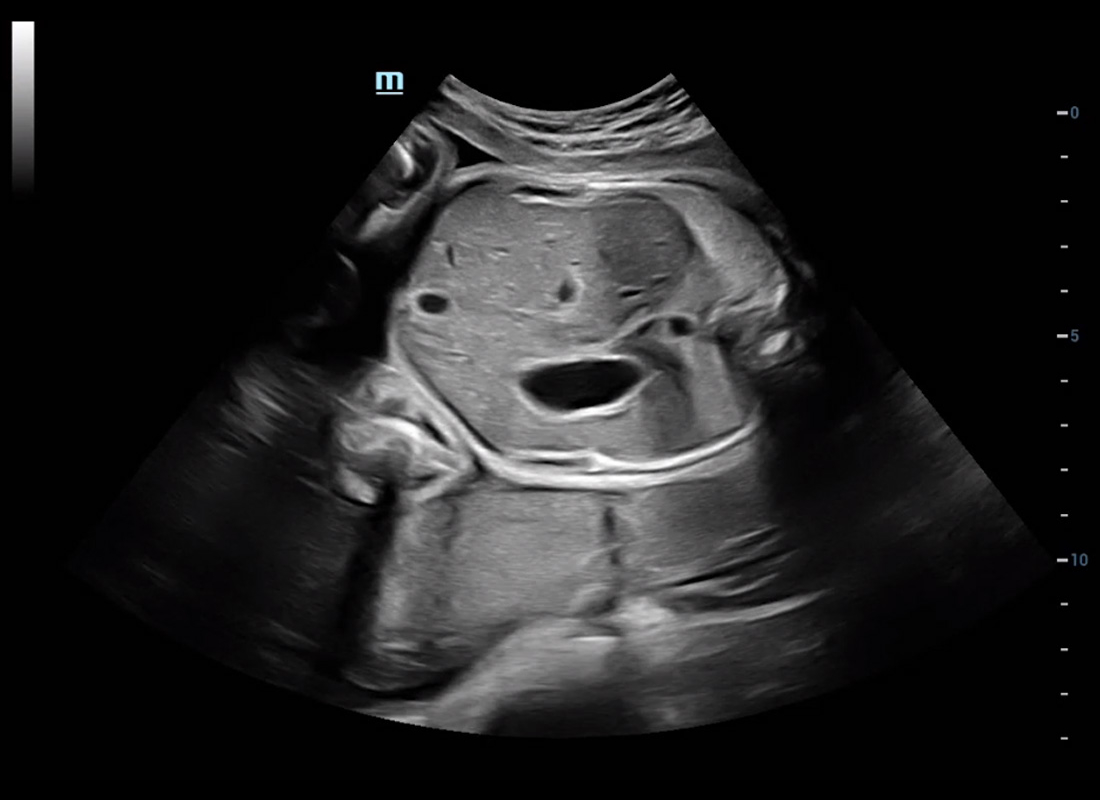

Central nervous system (CNS) malformations are one of the most common congenital abnormalities. Unfortunately, due to imaging limitations such as poor fetal position, acoustic shadowing, and operatorsŌĆÖ poor scanning skills, the MSP is particularly difficult to find in a 2D ultrasound. In this case, a faster and more user-friendly method, which automatically displays the standard planes together with the required measurements in a fetal CNS examination, could significantly boost both the quality and efficiency of clinical diagnoses.?NuewaŌĆÖs intelligent solution of fetal brain can realize automatic acquisition of brain volume data based on intelligent recognition of CNS application scenarios, intelligent generation of four fetal brain standard planes including MSP, automatic measurement of CNS biological items and automatic evaluation of fetal brain volume. More importantly, Nuewa's leading color Doppler technology can provide a clear and sensitive dynamic display of blood flow in the tiny vessels.